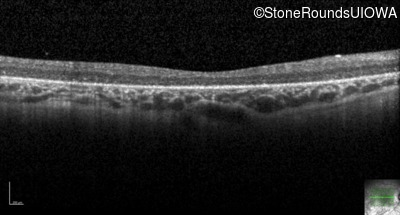

Optical Coherence Tomography - Right - 20/400 sc

Exemplar / OCT Stack